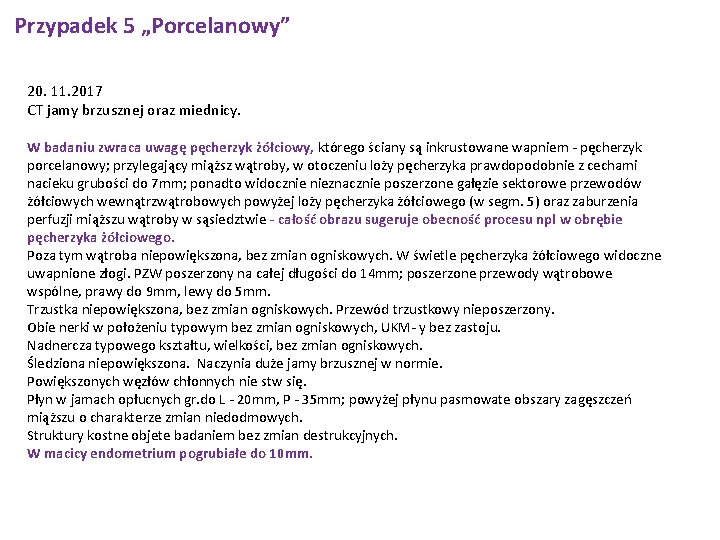

Przypadek 5 „Porcelanowy” 20. 11. 2017 CT jamy brzusznej oraz miednicy. W badaniu zwraca uwagę pęcherzyk żółciowy, którego ściany są inkrustowane wapniem - pęcherzyk porcelanowy; przylegający miąższ wątroby, w otoczeniu loży pęcherzyka prawdopodobnie z cechami nacieku grubości do 7 mm; ponadto widocznie nieznacznie poszerzone gałęzie sektorowe przewodów żółciowych wewnątrzwątrobowych powyżej loży pęcherzyka żółciowego (w segm. 5) oraz zaburzenia perfuzji miąższu wątroby w sąsiedztwie - całość obrazu sugeruje obecność procesu npl w obrębie pęcherzyka żółciowego. Poza tym wątroba niepowiększona, bez zmian ogniskowych. W świetle pęcherzyka żółciowego widoczne uwapnione złogi. PZW poszerzony na całej długości do 14 mm; poszerzone przewody wątrobowe wspólne, prawy do 9 mm, lewy do 5 mm. Trzustka niepowiększona, bez zmian ogniskowych. Przewód trzustkowy nieposzerzony. Obie nerki w położeniu typowym bez zmian ogniskowych, UKM- y bez zastoju. Nadnercza typowego kształtu, wielkości, bez zmian ogniskowych. Śledziona niepowiększona. Naczynia duże jamy brzusznej w normie. Powiększonych węzłów chłonnych nie stw się. Płyn w jamach opłucnych gr. do L - 20 mm, P - 35 mm; powyżej płynu pasmowate obszary zagęszczeń miąższu o charakterze zmian niedodmowych. Struktury kostne objete badaniem bez zmian destrukcyjnych. W macicy endometrium pogrubiałe do 10 mm.

Przypadek 5 „Porcelanowy” Chorą konsultowano ponownie chirurgicznie 21. 11. 2017 (dr Kaczka) - zalecono wyznaczenie planowego terminu przyjęcia do Kliniki Chirurgii za około tydzień (po wyrównaniu hipertyreozy - wartości FT 3, FT 4 powinny być w zakresie normy). Oznaczono ponadto poziom markerów nowotworowych – Ca 125 236. 3, norma do 35), pozostałe markery w normie.

Przypadek 5 „Porcelanowy” q Marker Ca 125 - wartość 236. 3 (norma do 35) q Pęcherzyk żółciowy porcelanowy, miąższ wątroby w ok. pęcherzyka prawdopodobnie nacieczony q Płyn w jamie opłucnowej, zmiany niedodmowe q W badaniu cytologicznym płynu- cellulae atypicae, probaliter carcinomatosae q Pogrubienie endometrium do 10 mm q W lewym płacie tarczycy hypodensyjne zmiany ogniskowe z obecnością zwapnień